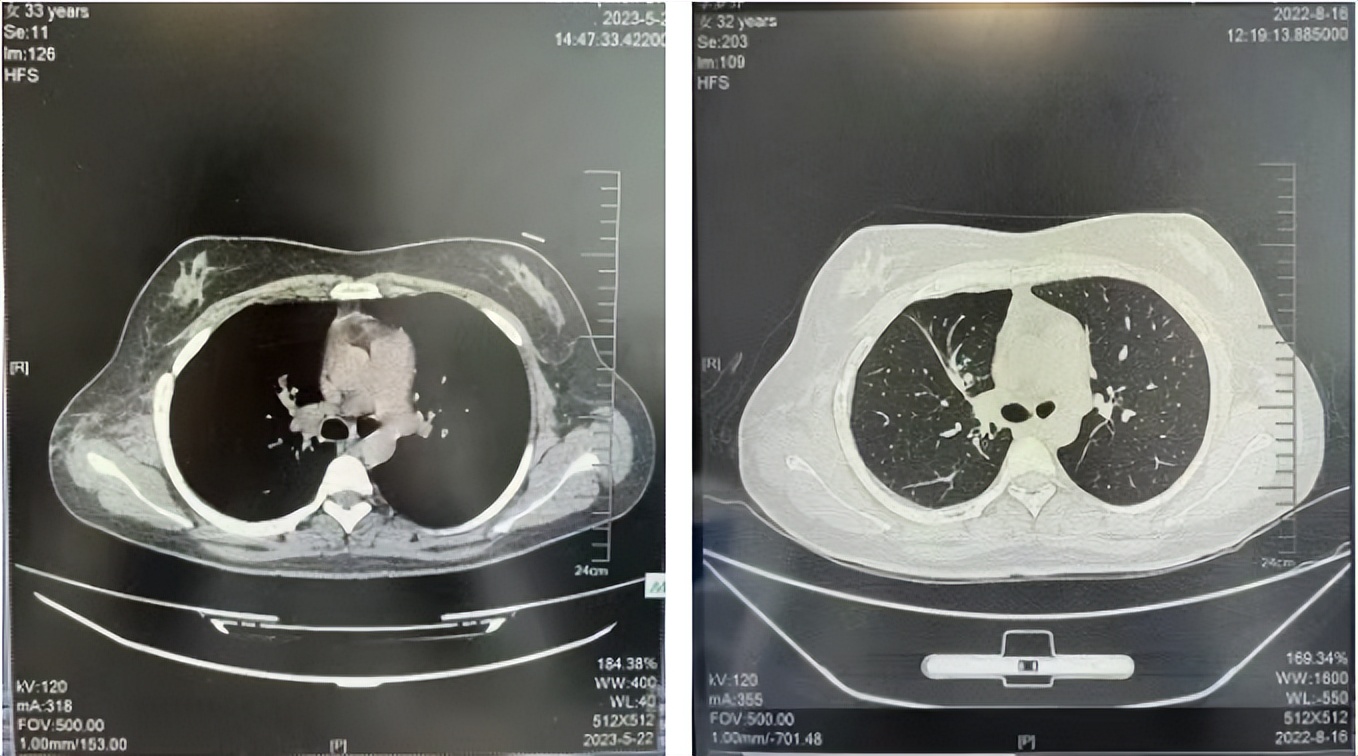

治疗经过:2023年3月27日始行恩沙替尼靶向治疗至今,最佳疗效为PR,末次评效为维持PR。期间出现轻度肝功能异常(DILI 1级),对症处理后好转。截止目前PFS为26个月。

2024年6月复查PR(最佳疗效)

2024年12月复查维持PR

2025年3月复查维持PR